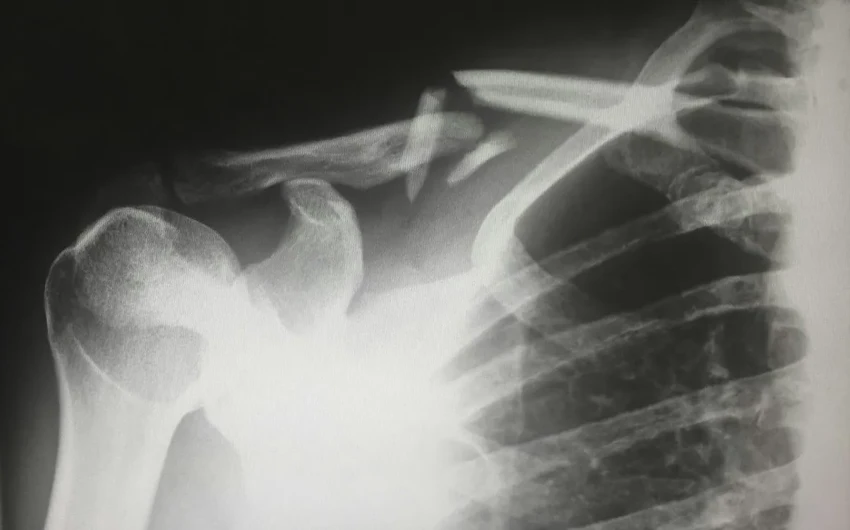

Стандартный метод диагностики — DXA-сканирование, которое меряет минеральную плотность кости. Это хорошо, но не идеально. Качество самой костной ткани, её микроархитектура, тоже играет огромную роль в прочности. Но долгое время оставался открытым вопрос: а как на эту хрупкую конструкцию влияют жировые отложения? Неужели лишний вес — это не только нагрузка на суставы, но и что-то более глубокое?

Низкое качество губчатой (трабекулярной) кости в позвонках было связано с большим количеством висцерального жира — того самого, что обволакивает внутренние органы. Но самое интересное ждало дальше. Когда учёные изучили распределение подкожного жира, выяснилось: чем больше жировой массы на руках, тем хуже качество и прочность костей позвоночника. Связь нашли именно с руками — не с бёдрами или голенями.